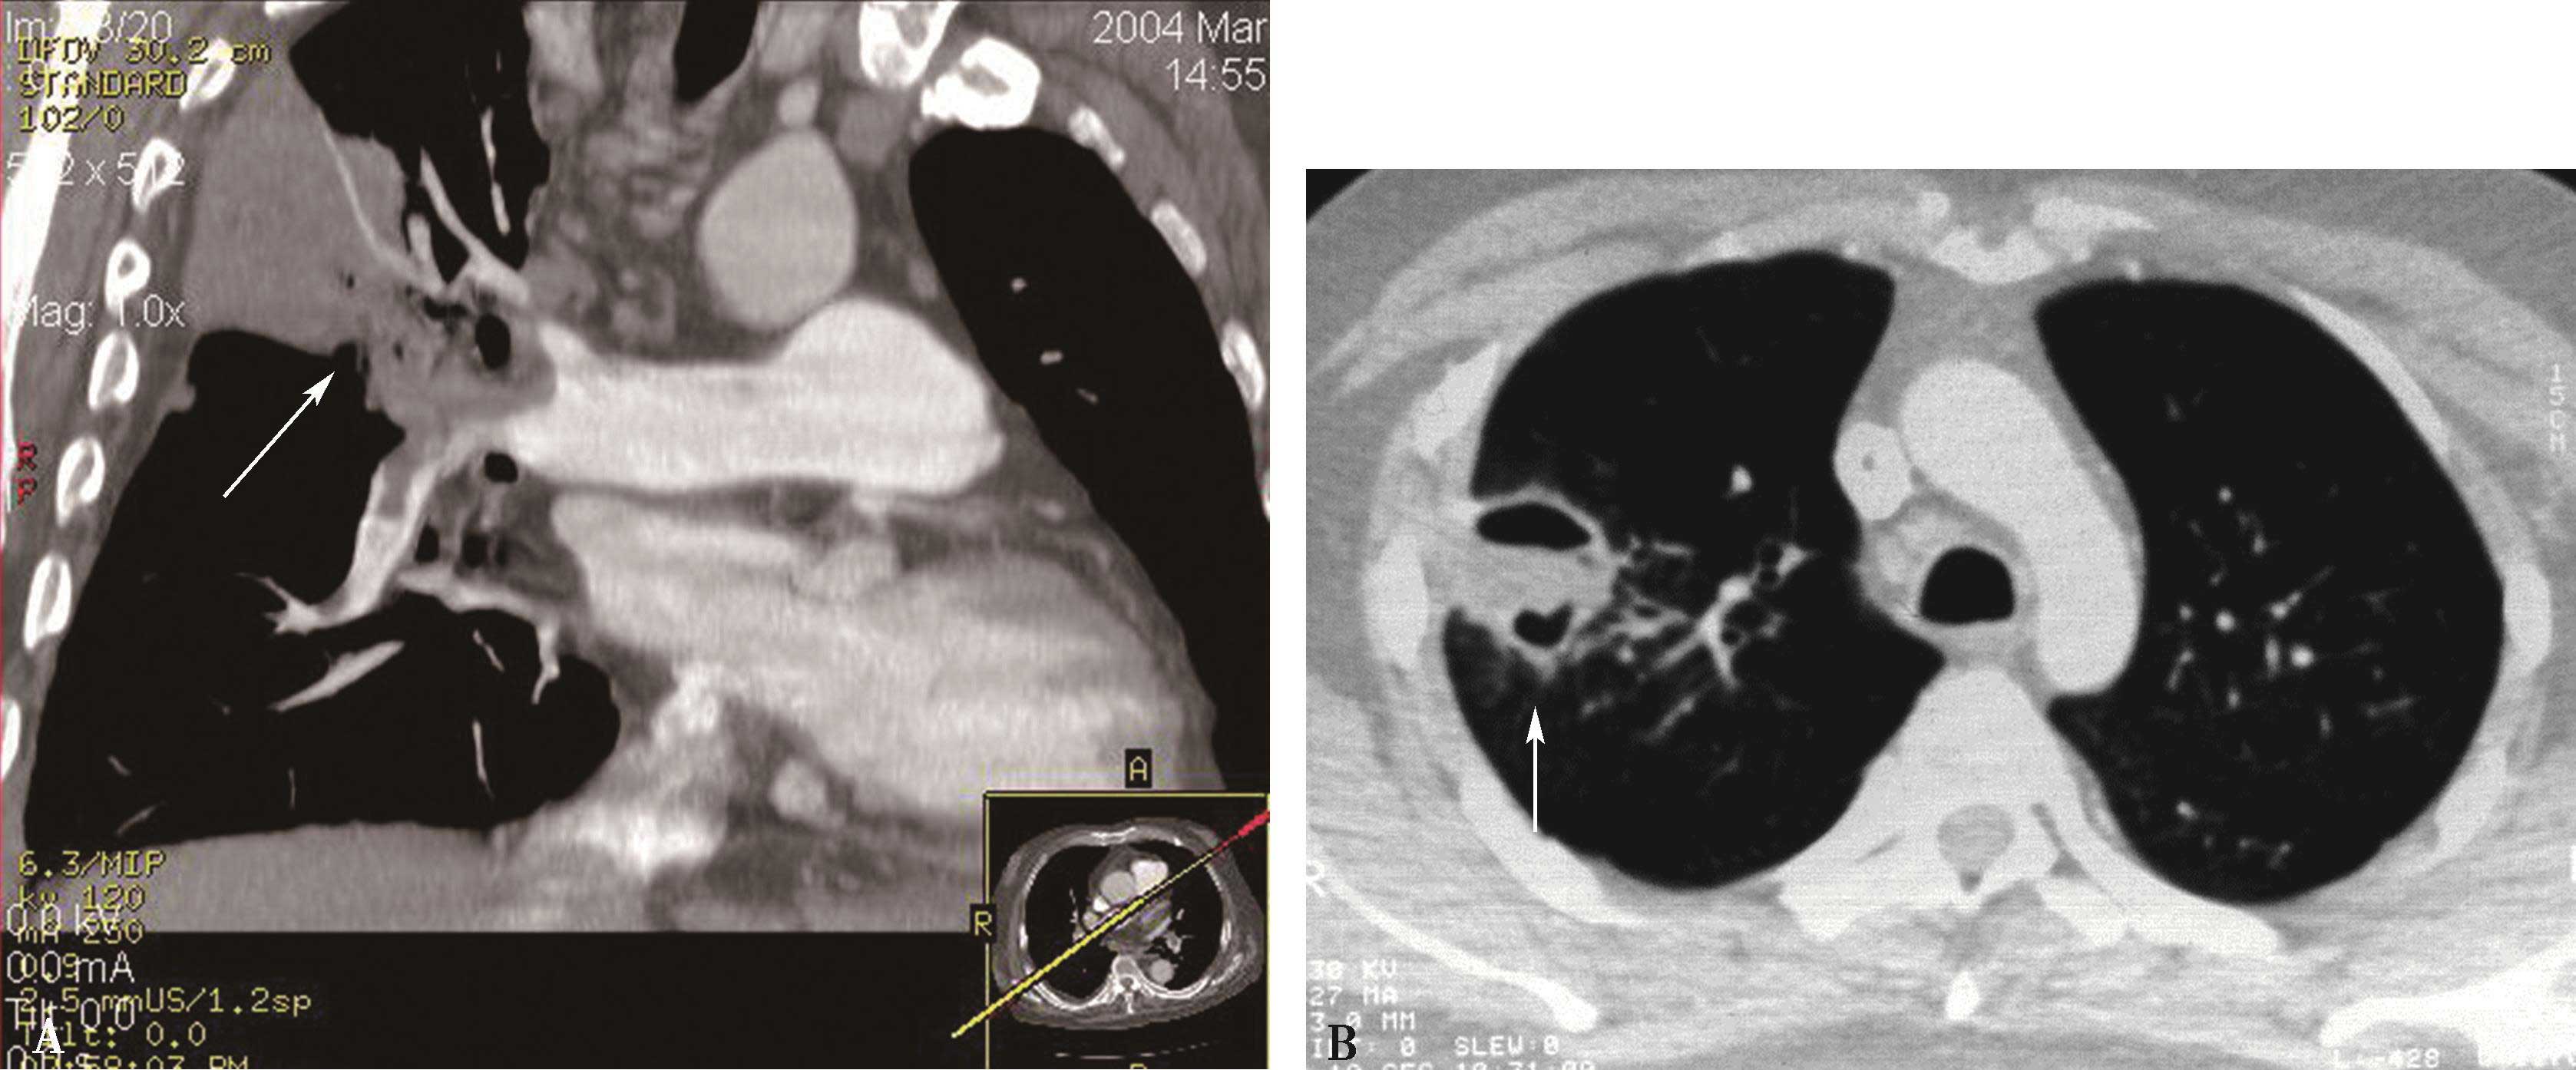

3.CT双能量成像技术应用于肺动脉造影成像时,可以采用自动识别彩色编码功能,能够对血管进行选择性色彩编码,从而提示可能的发生栓塞的肺血管,尤其是细小的肺血管,从而提高微小栓子的检出率,降低漏诊率(图8-1-10)。

图8-1-10 双源CT双能成像,显示左肺舌叶及下叶肺段及亚分段小分支栓塞,灌注缺损;彩色编码,使得图像清晰,利于观察,提高诊断检出率(↑)